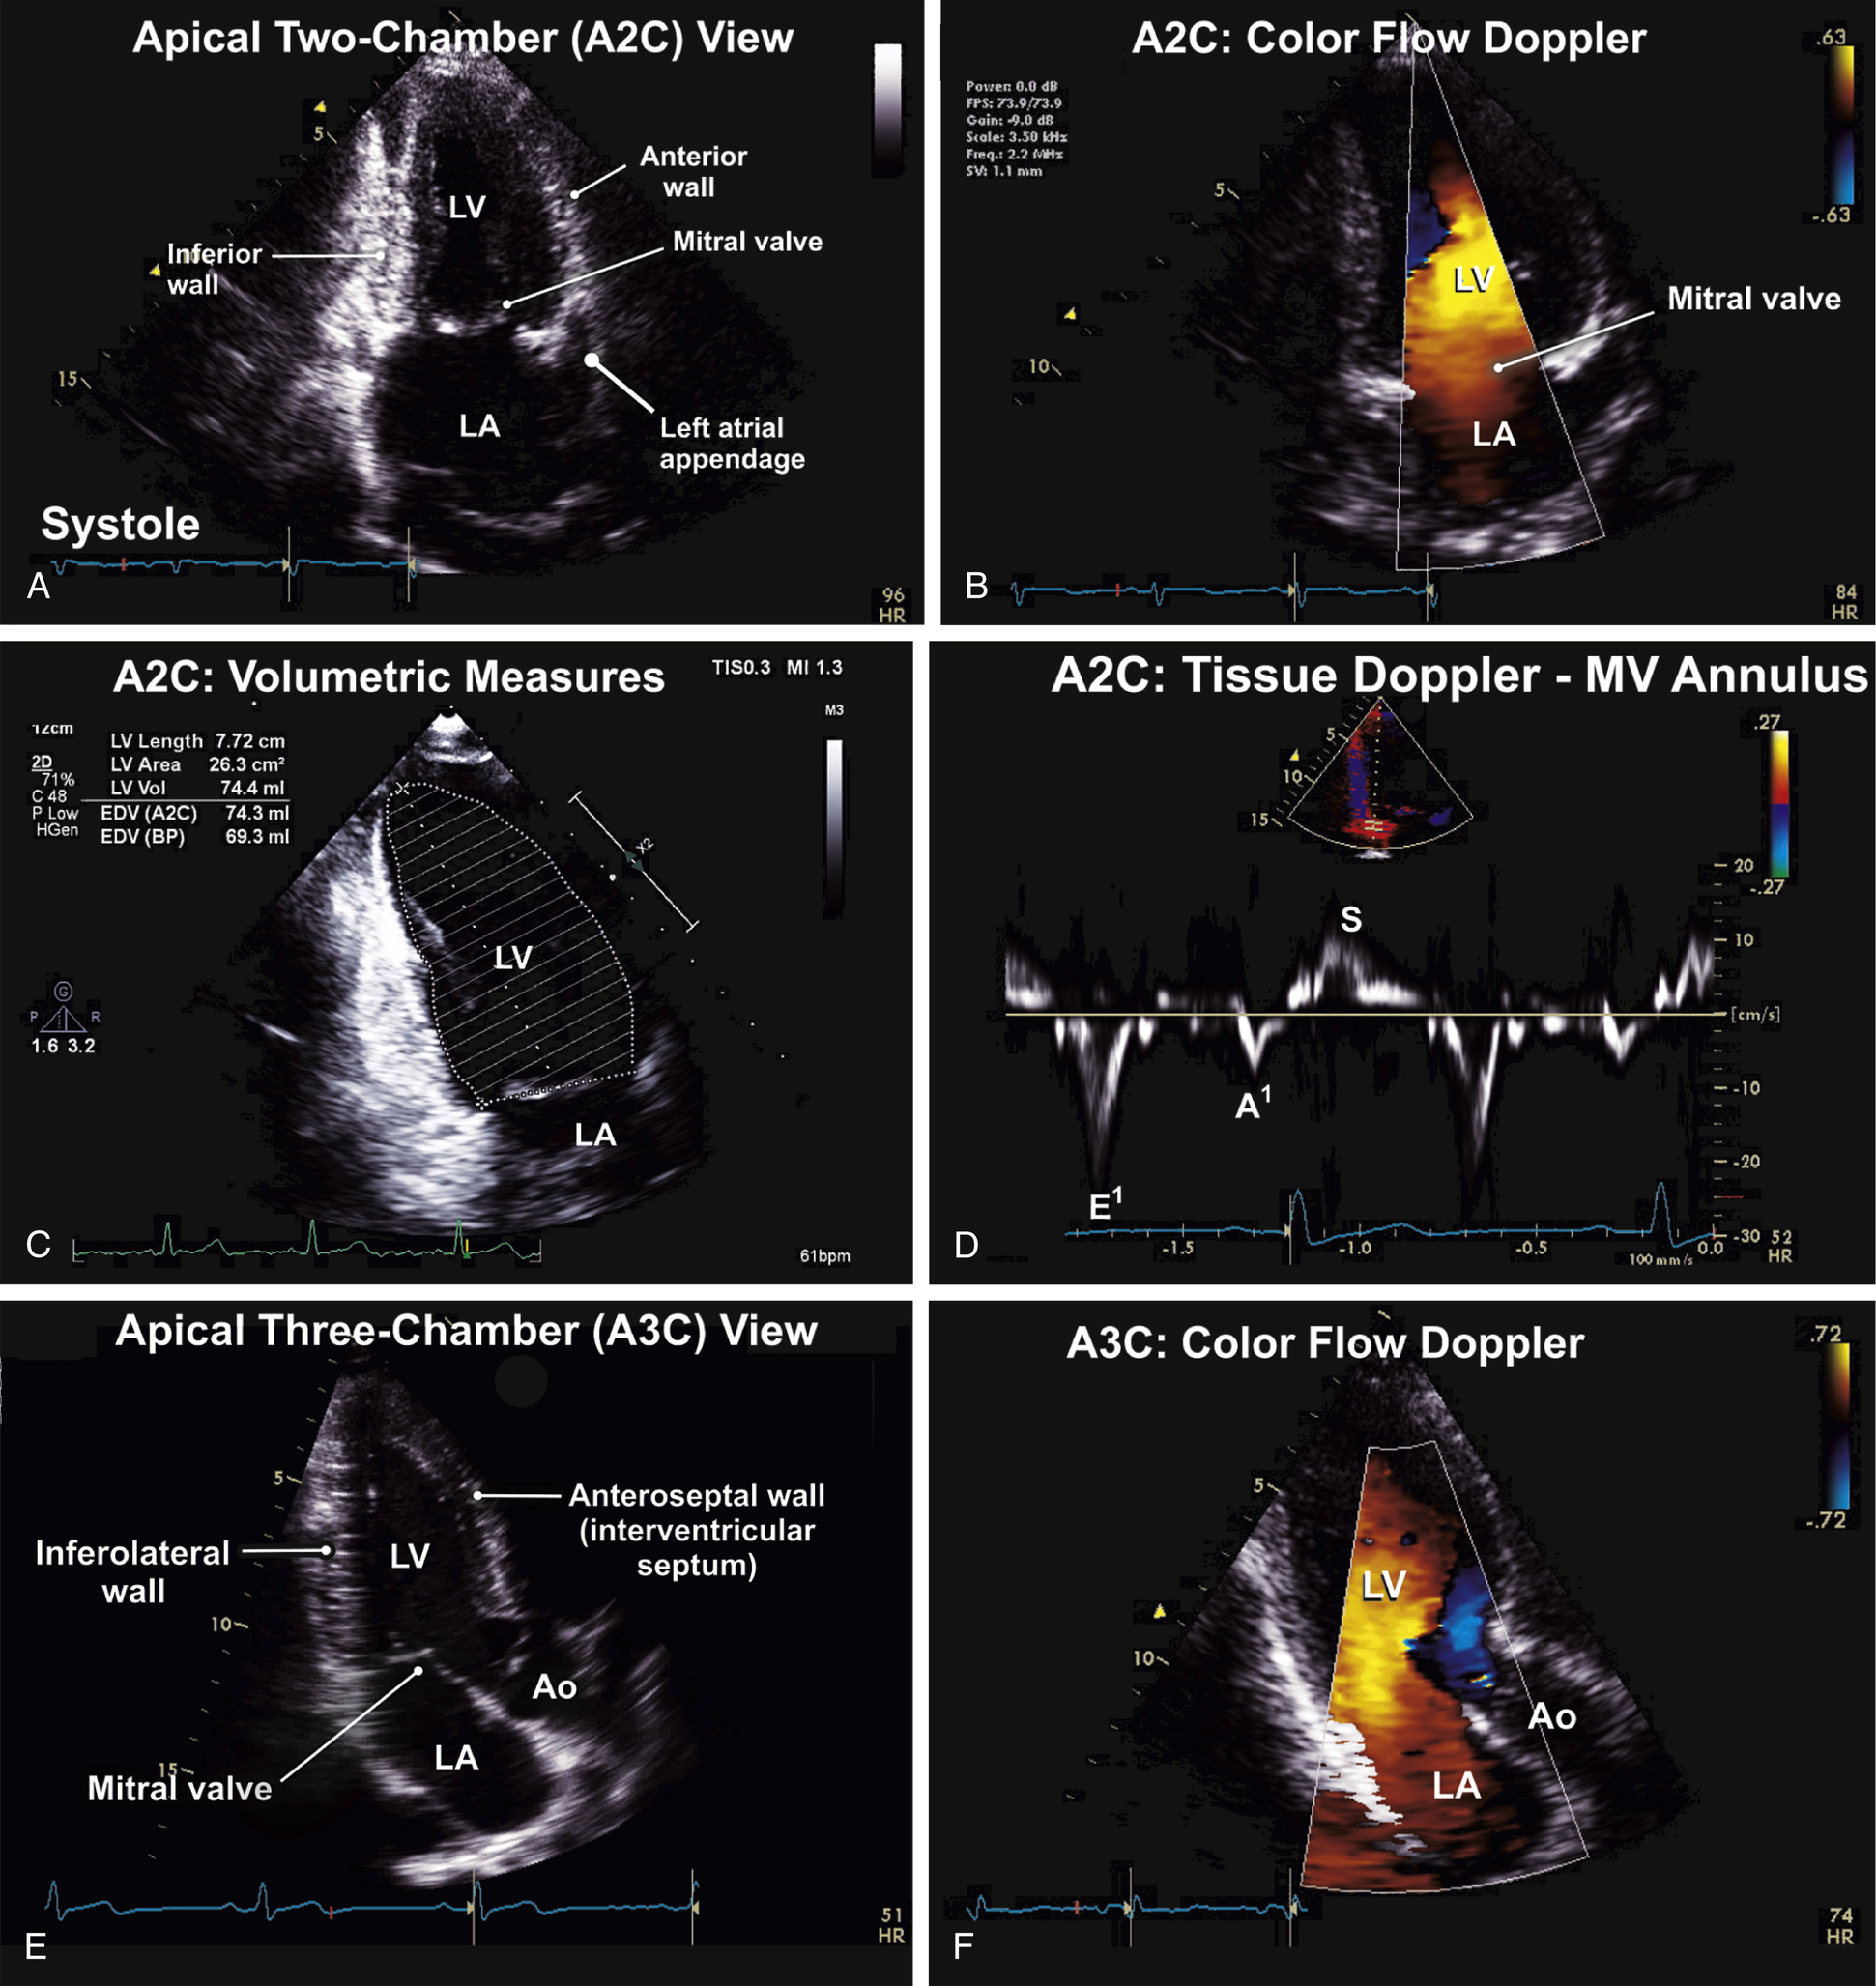

Apical Views (see Figs. 9.5–9.8)

| Transducer Position (Window) | 2d ± M-Mode ± 3d | CFD | Spectral Doppler Pw, Cw | Tissue Doppler Imaging (Tdi) |

| Apical two-chamber view (A2C) | 2D image | CFD to MV | TDI (PW) of MV annulus (anterior and inferior) Color TDI to LV walls | |

Apical three-chamber view (A3C) or apical long-axis (ALAX) view | 2D image for wall motion evaluation | CFD to AV and MV | — | — |